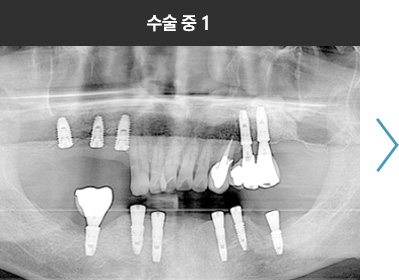

BMP를 이용한 수술 사례      I

치료 기간 : 2023.03.22 ~ 2023.09.15

* 상기 사례의 경우, 해당 의료기관에서 진료를 한 환자분의 동의를 얻어 사용되었습니다. * 치료 전후의 사진은 동일 인물과 동일한 조건에서 촬영 되었음을 알려드립니다.

* 모든 수술 및 시술은 개인에 따라 부작용고지 : 임플란트치료는 치료 후 감염,

염증, 연조직합병증, 출혈, 감각이상 등의 부작용이 있을 수 있습니다.

의료진과 충분히 상의 후 신중하게 결정하시기를 바라겠습니다.